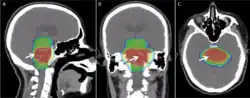

Radiation therapy for a patient with a diffuse intrinsic pontine glioma, with radiation dose color-coded